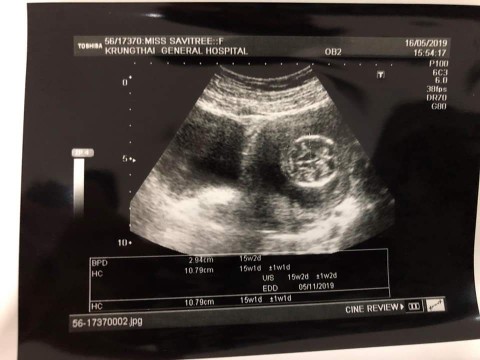

รูปตอน14weekค่ะ ตอนนี้ 18weekแล้วค่ะ

บ้านนี้ซาวครั้งเเรกตอน3เดือนค่ะ